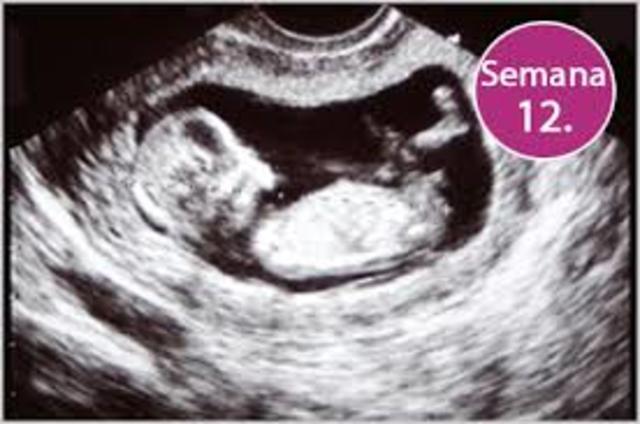

• Semana 11

Semana 11

-Se crea cimientos de sus primeros pasos, reflejo patelar.

-Primera econografía.

-El feto aumenta 5 veces su tamaño.

-Mide 7 cm de largo

• Semana 12

Semana 12

-El feto entra al segundo trimestre.

-Existe menos riesgo de aborto.

-El feto sobresa desde ángulos diferentes.